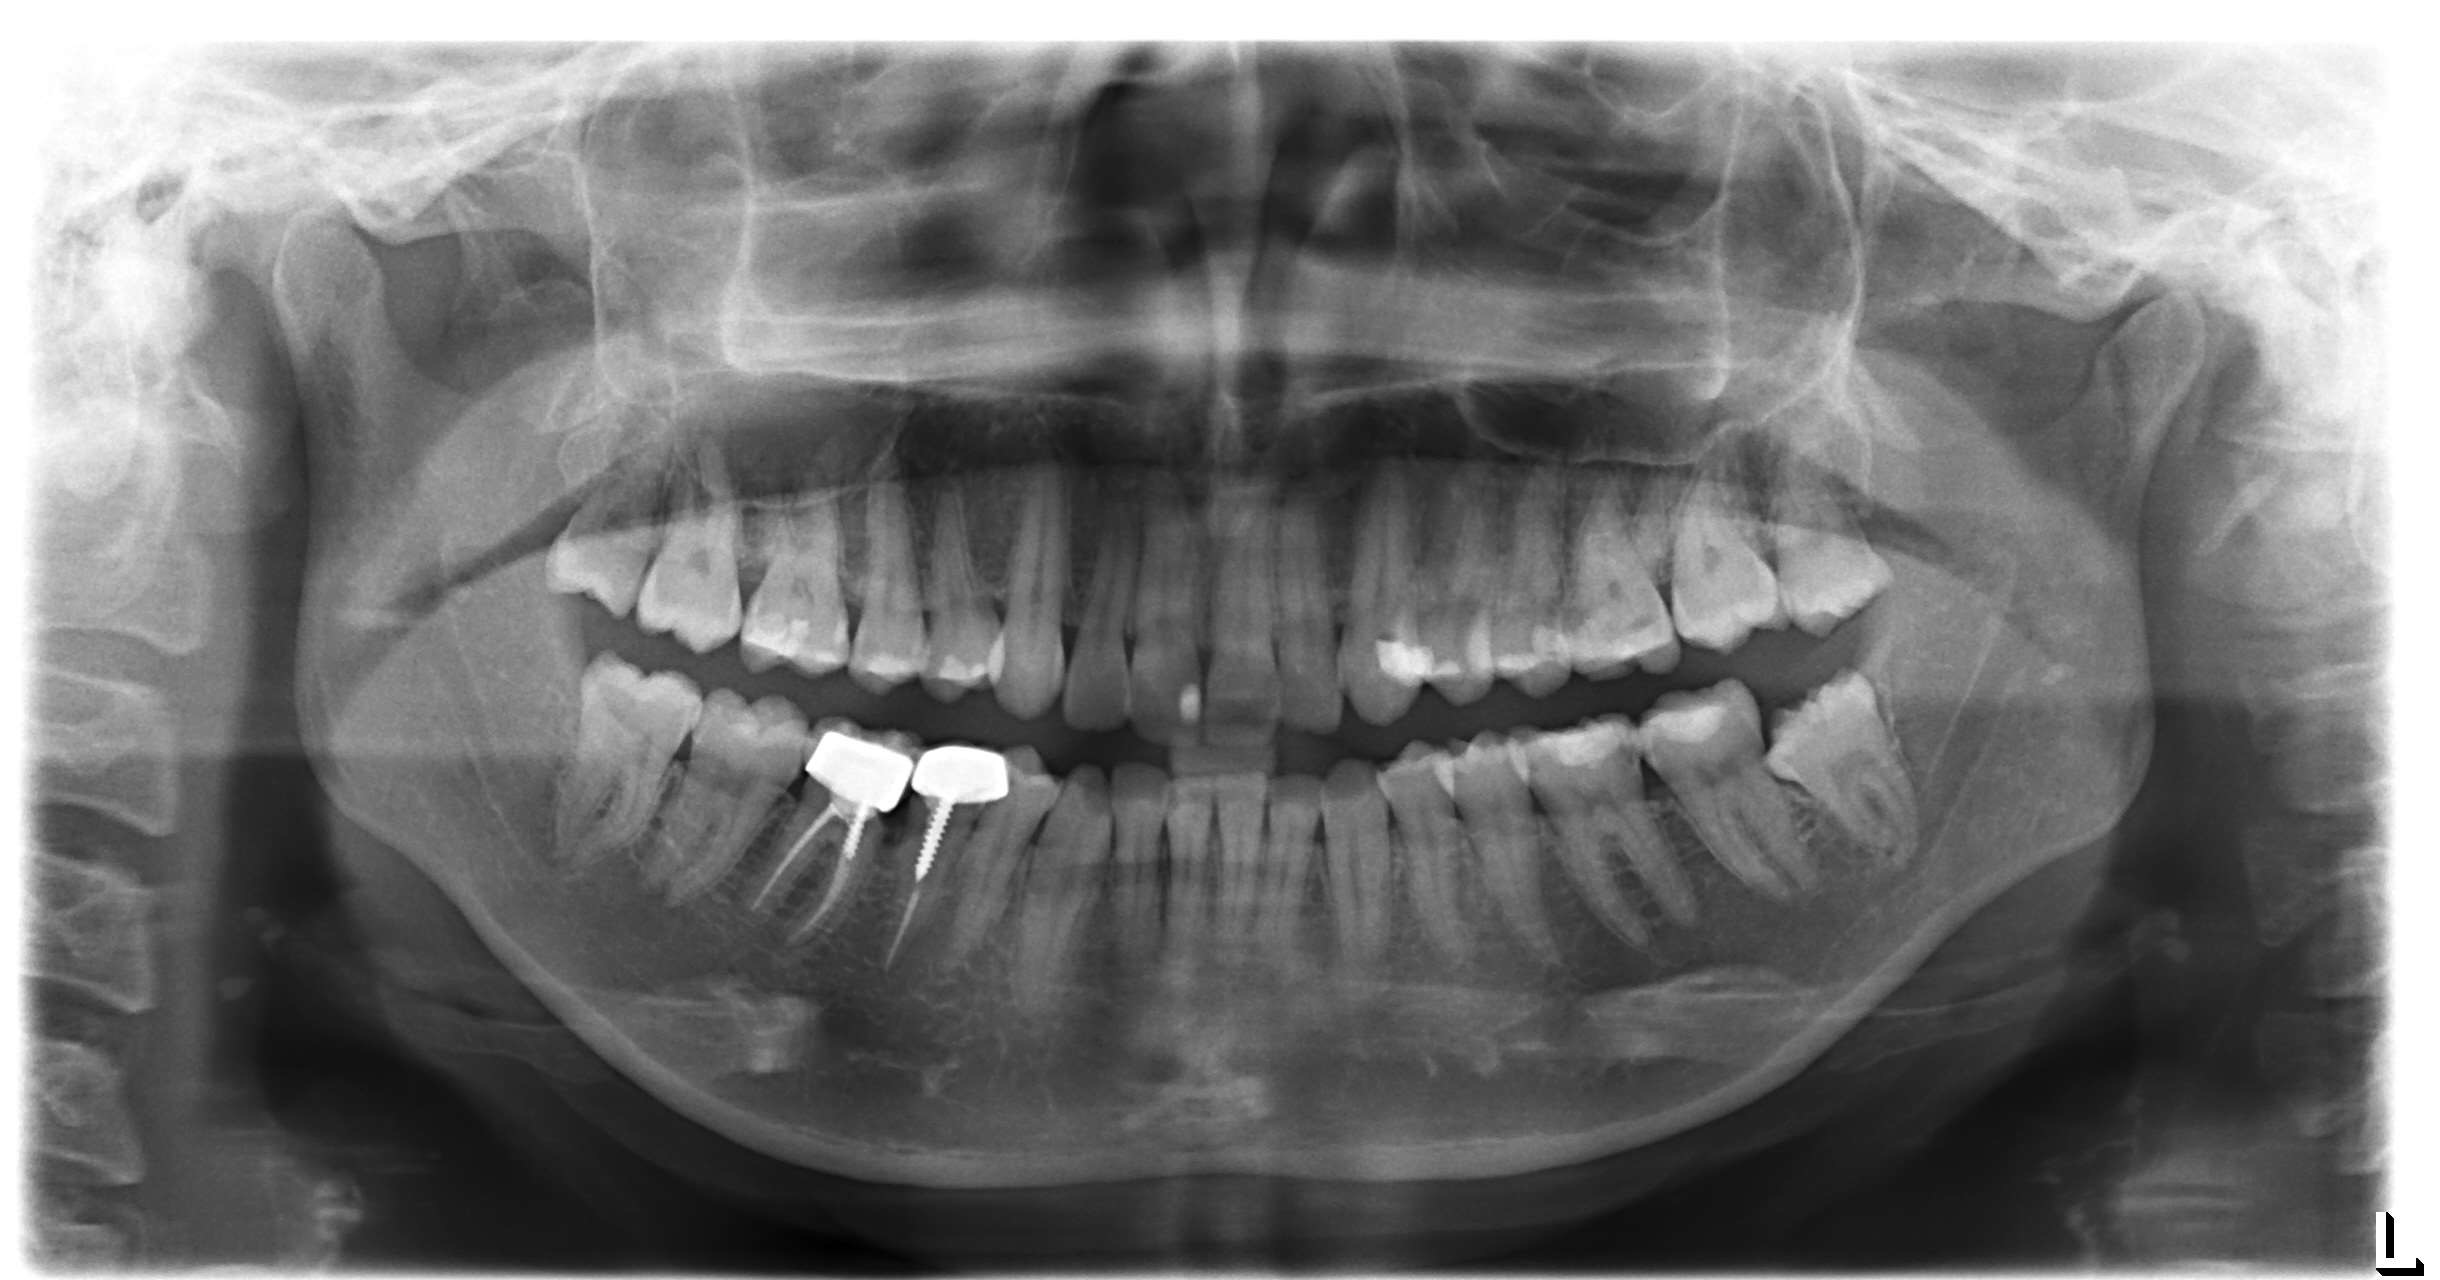

أعاني من الم في تلبيسة الاسنان ( سنين) مع نزيف دم عند استخدام خيط الاسنان

IMG_6199 IMG_6200